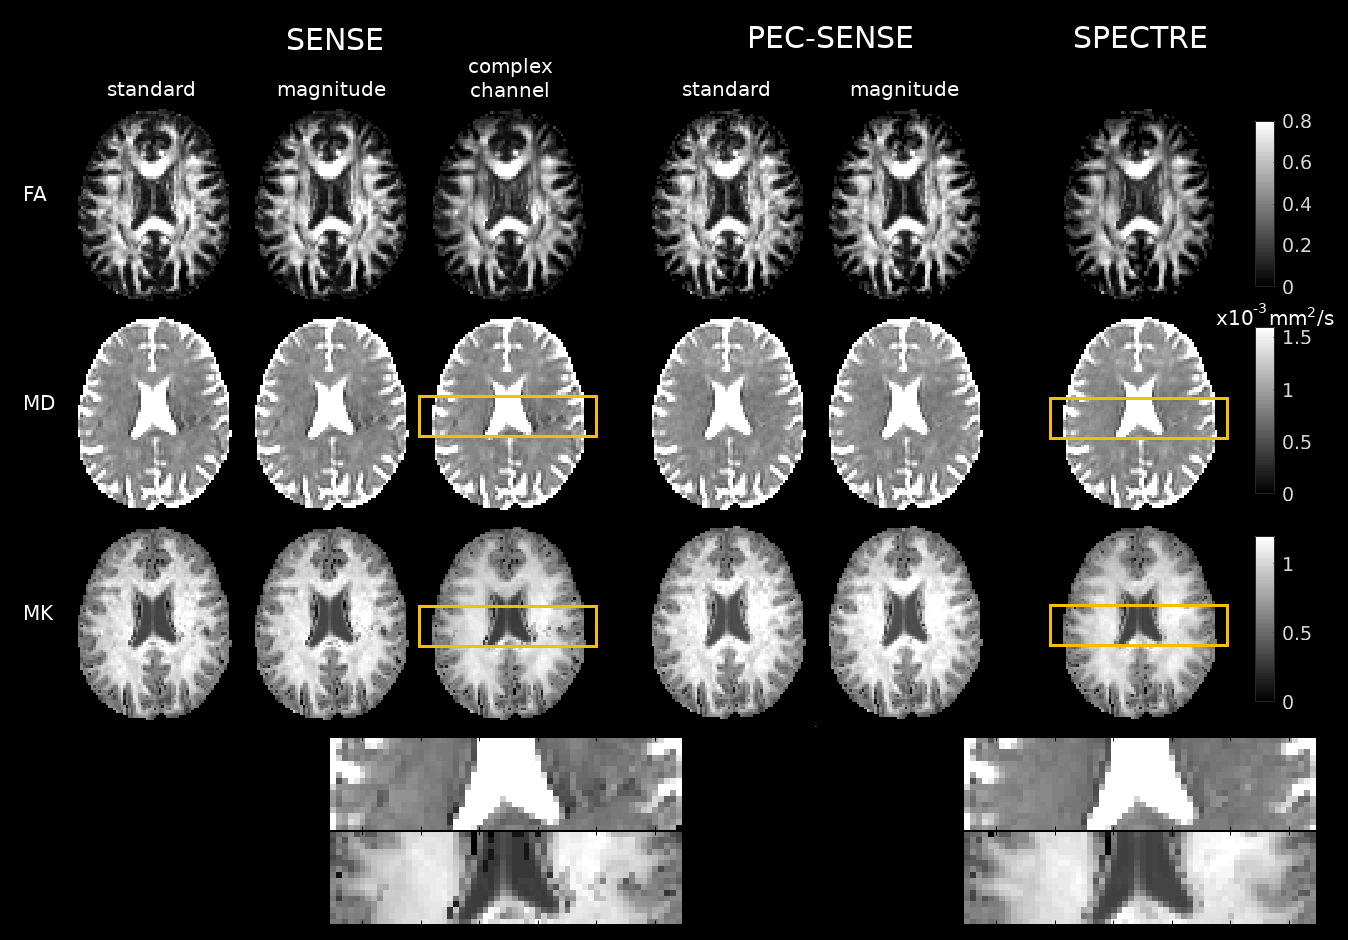

Fig. 2. Ghosting artefacts were visible in the SENSE reconstructions (left, yellow outline), while noise amplification was present at high b-values in the standard and magnitude PEC-SENSE reconstructions (middle, purple outline). Denoising complex channel data during a 2D phase-corrected reconstruction both mitigated ghosting artefacts (right, yellow outline) and limited noise propagation (right, purple outline). Note the noise-floor was also significantly reduced in complex channel denoised data (CSF in purple outlined region, right).

Fig. 3. Residual ghosting in SENSE reconstructions introduced appreciable local biases into MD and MK maps (left, yellow zoomed regions). Phase correction in PEC-SENSE removed biases from ghosting (right, yellow zoomed regions); however, MK estimates in standard and magnitude denoised PEC-SENSE reconstructions appeared inflated on visual inspection. These noise-related biases in MK were less apparent in SPECTRE.